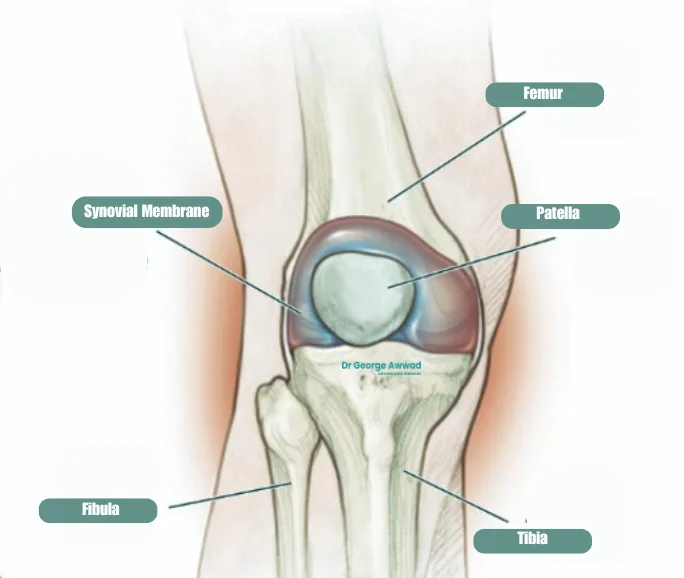

• Tibial Tubercle Osteotomy

Tibial Tubercle Osteotomy